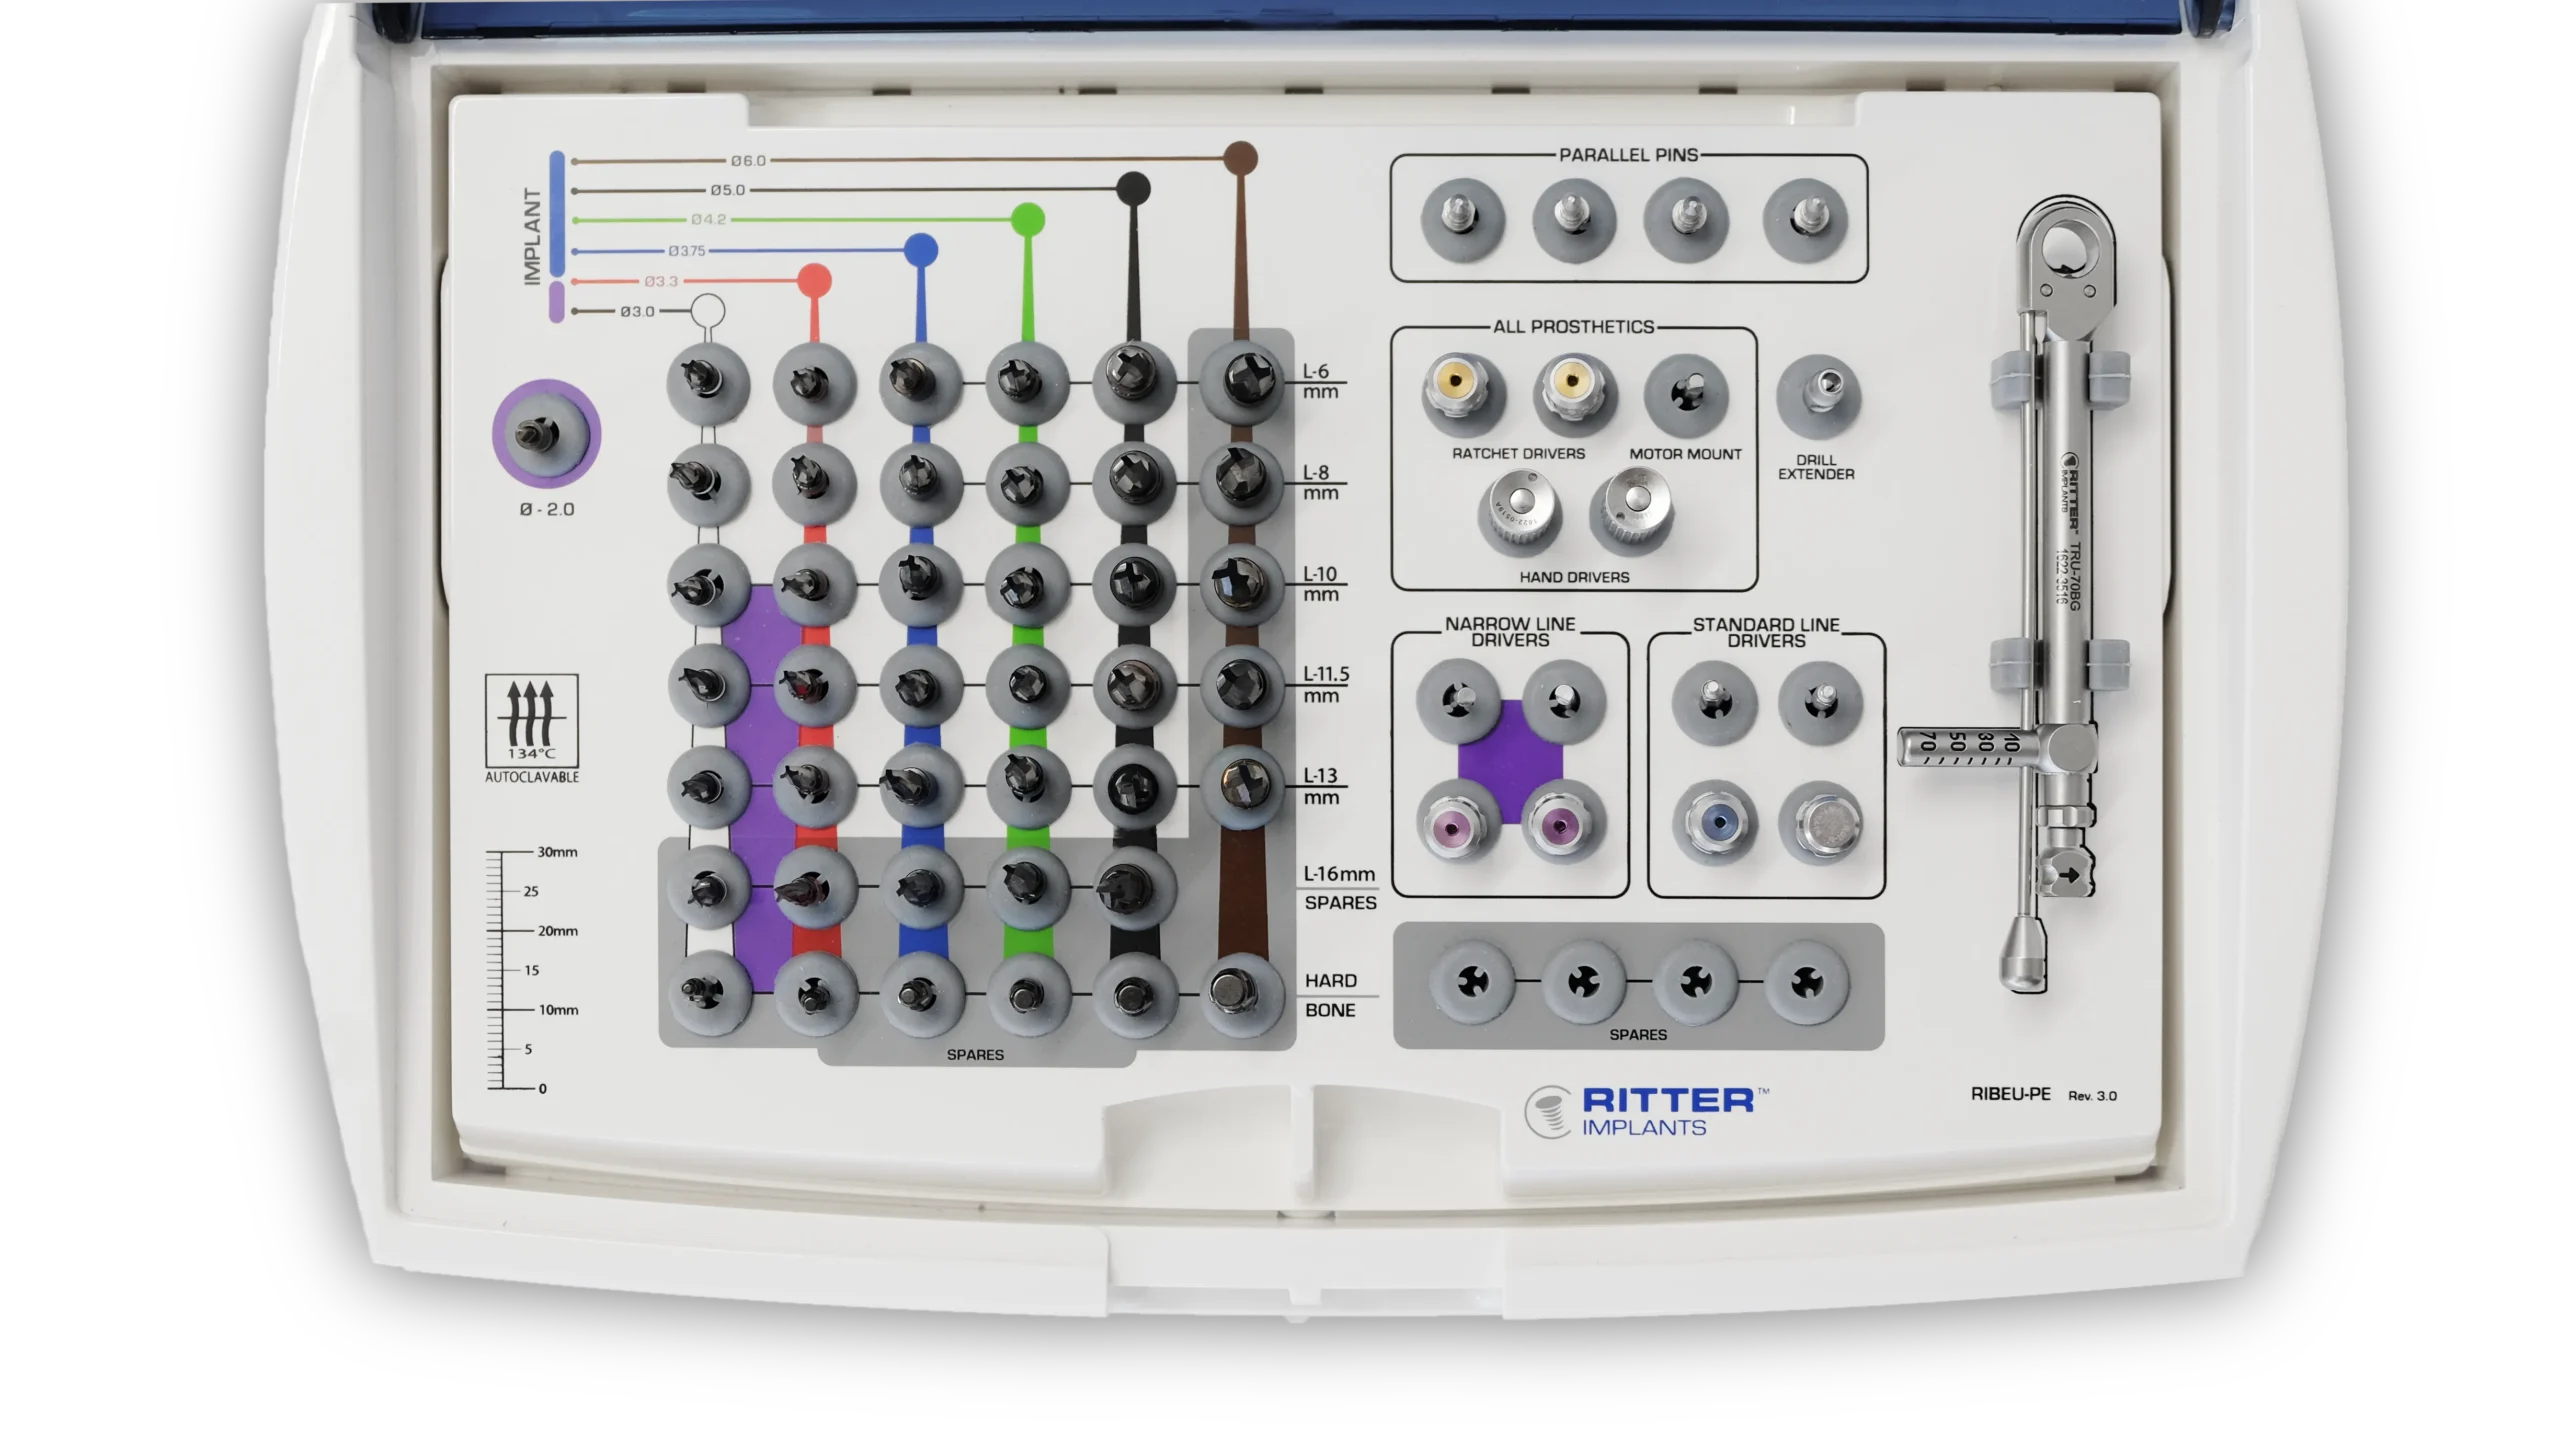

Quy trình mũi khoan

Nên sử dụng mũi khoan mồi 2.0 mm cho tất cả các đường kính implant. Các implant có đường kính 3.0 mm và 3.3 mm (Dòng Hẹp – Narrow Line) cùng với implant đường kính 3.75 mm (Dòng Tiêu Chuẩn – Standard Platform) nên được đặt ngang mức đỉnh xương. Các implant đường kính 4.2 mm, 5.0 mm và 6.0 mm (Dòng Tiêu Chuẩn – Standard Platform) có thể được đặt dưới mức đỉnh xương